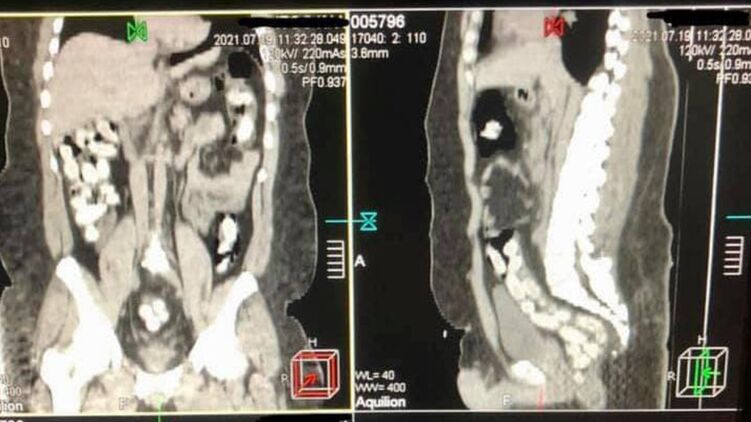

Курьер проглотил 90 капсул с кокаином. Фото: Госпогранслужба

"В июле 2021 года в Борисполе был задержан бразилец, который в желудке ввез в Украину почти 1 кг кокаина. Мужчина проглотил 90 капсул, которые извлекали из кишечника медикаментозным путем после компьютерной томографии", - говорится в сообщении.

Напомним, 29-летний курьер с начиненными кокаином капсулами в желудке прибыл в аэропорт "Борисполь". Имея предварительную оперативную информацию, таможенники применили в отношении иностранца личный досмотр с привлечением медицинского работника. Процедура проходила в медицинском учреждении с применением компьютерной томографии брюшной полости мужчины.

Изъятие 90 капсул овальной формы, которые находились в его кишечнике, происходило медикаментозным путем и длилось почти три часа.